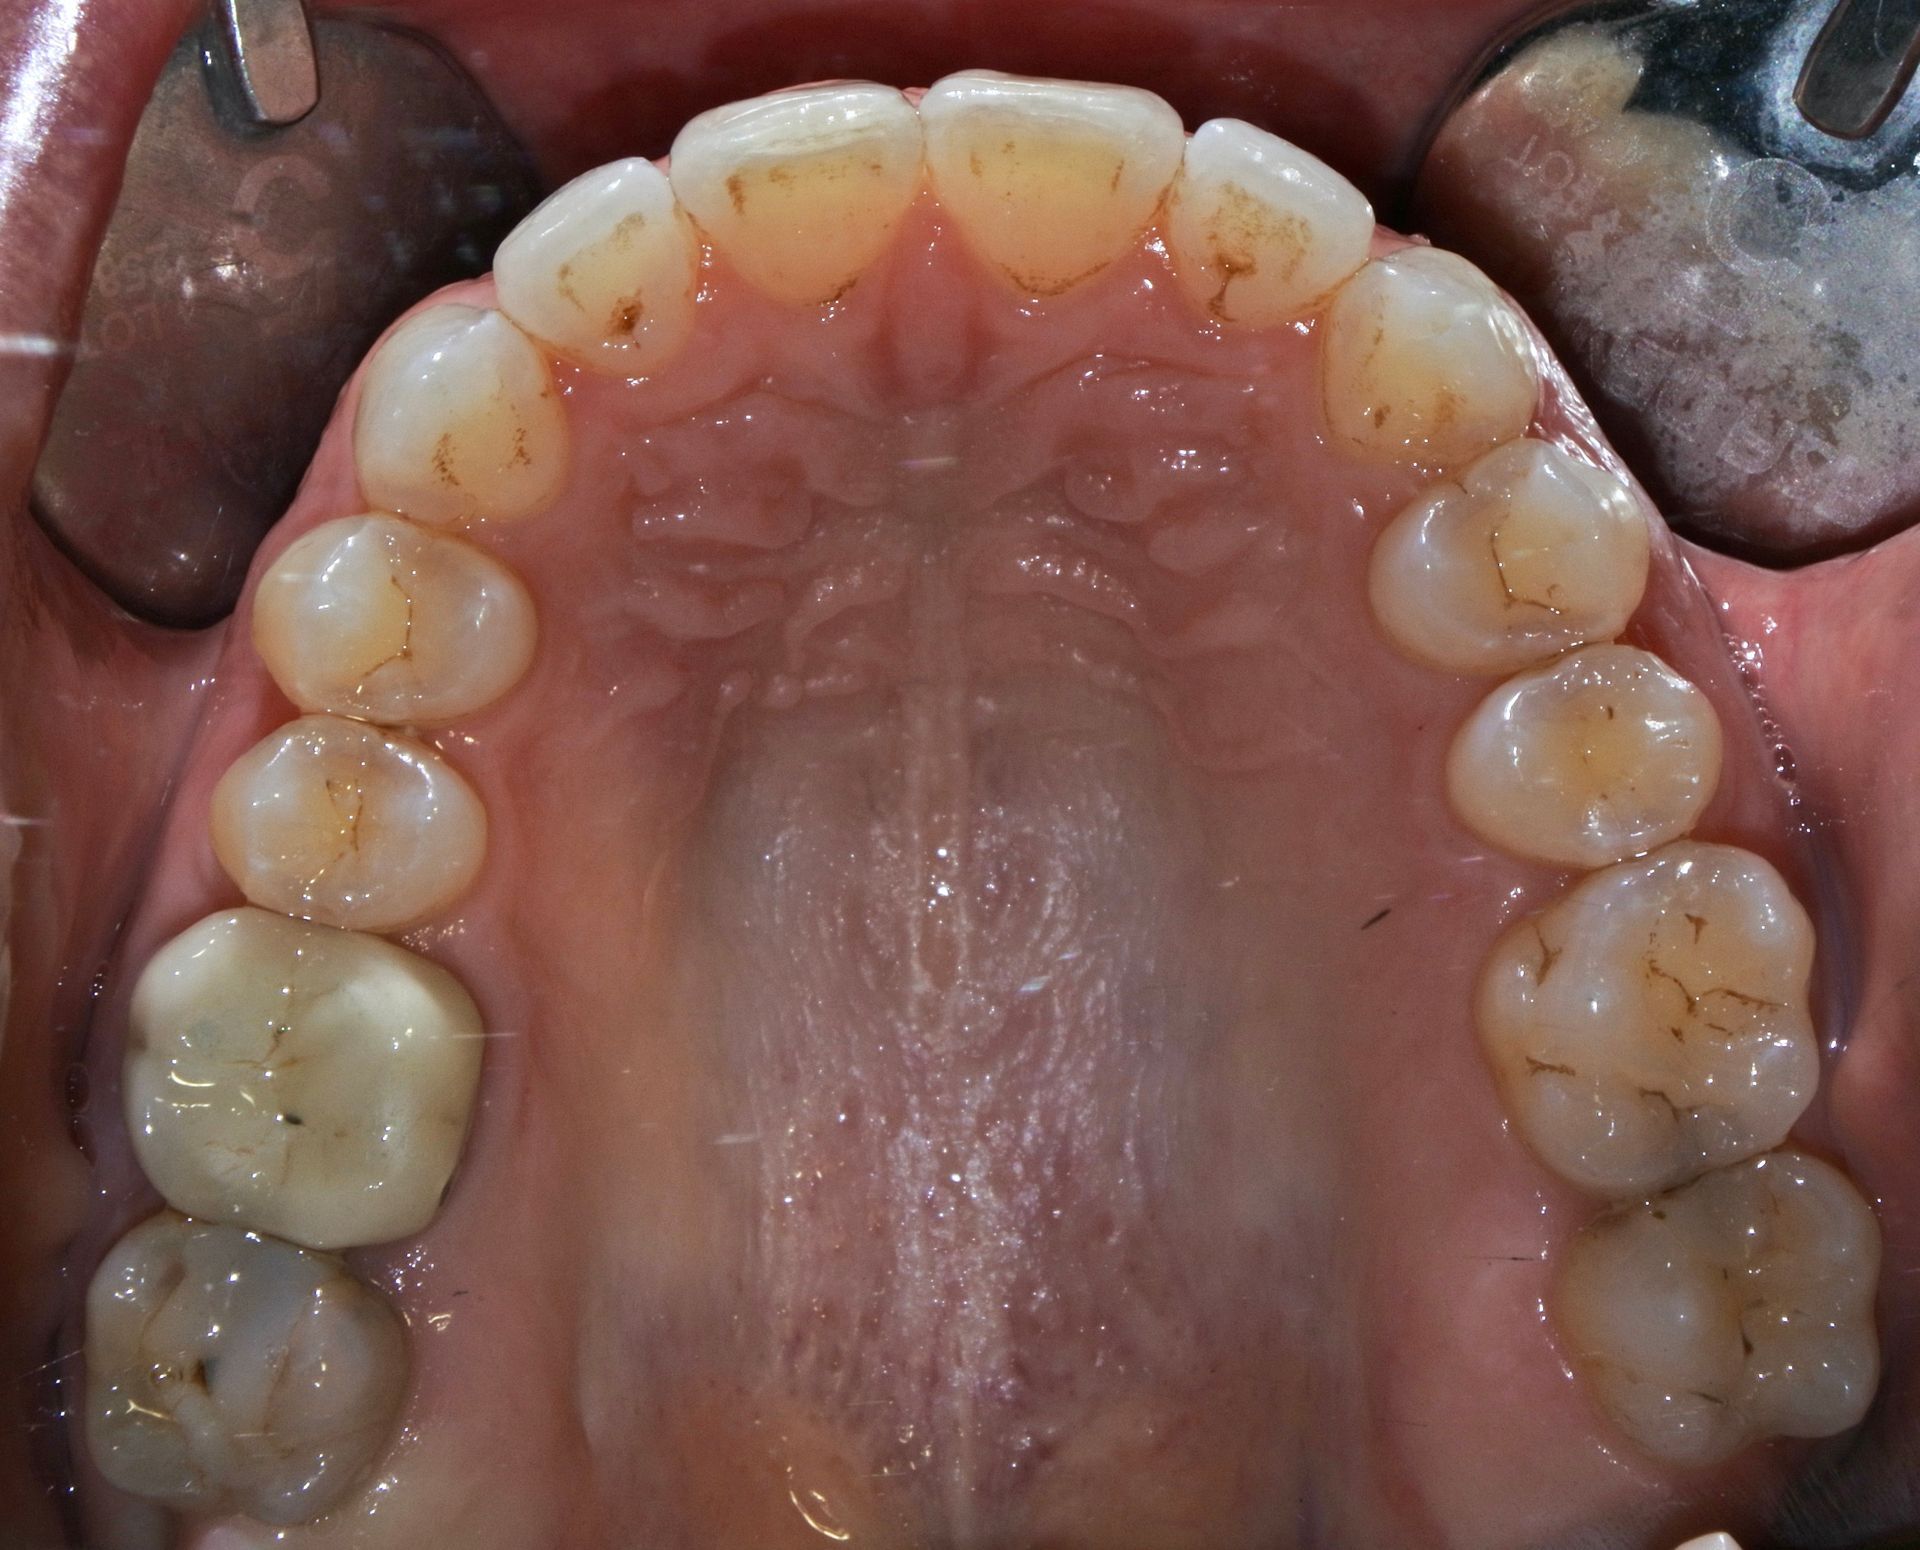

INVISALIGN è un sistema di mascherine trasparenti (aligner) studiato per permettere una elevata predicibilità dei movimenti dentali e della durata del trattamento.

Si tratta di una soluzione invisibile ed efficace per l'allineamento graduale dei denti.

Ciascun singolo movimento migliora il sorriso, in modo delicato.